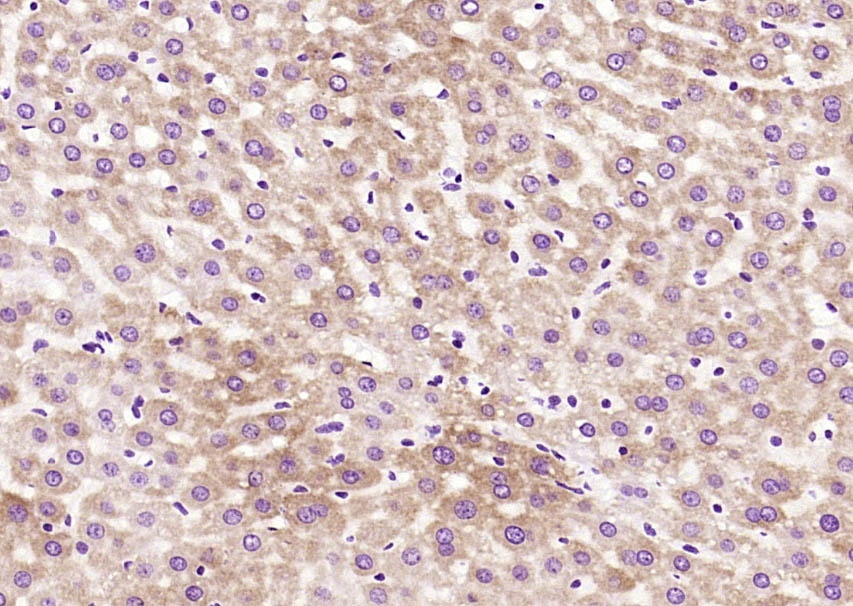

Paraformaldehyde-fixed, paraffin embedded (rat brain); Antigen retrieval by boiling in sodium citrate buffer (pH6.0) for 15min; Block endogenous peroxidase by 3% hydrogen peroxide for 20 minutes; Blocking buffer (normal goat serum) at 37°C for 30min; Antibody incubation with (CHERP) Polyclonal Antibody, Unconjugated (bs-13898R) at 1:200 overnight at 4°C, followed by operating according to SP Kit(Rabbit) (sp-0023) instructionsand DAB staining.

Paraformaldehyde-fixed, paraffin embedded (rat liver); Antigen retrieval by boiling in sodium citrate buffer (pH6.0) for 15min; Block endogenous peroxidase by 3% hydrogen peroxide for 20 minutes; Blocking buffer (normal goat serum) at 37°C for 30min; Antibody incubation with (CHERP) Polyclonal Antibody, Unconjugated (bs-13898R) at 1:200 overnight at 4°C, followed by operating according to SP Kit(Rabbit) (sp-0023) instructionsand DAB staining.